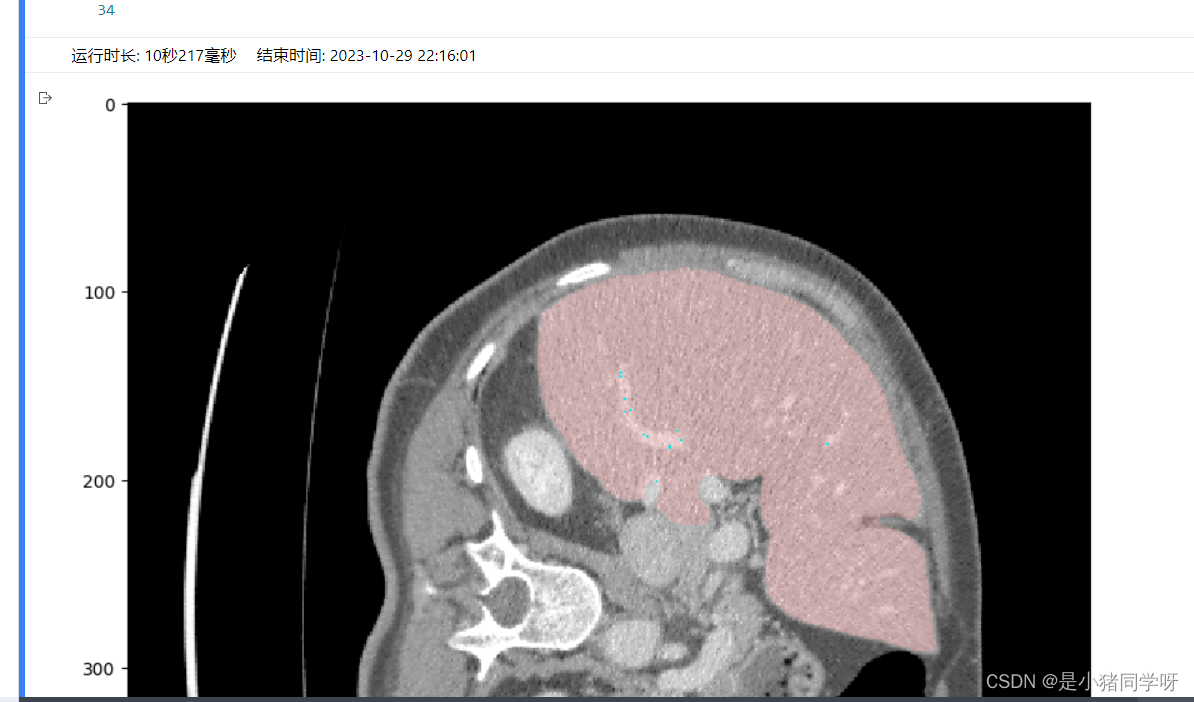

经过测试,肝脏和肝脏肿瘤分割系统的各项功能都能够正常工作,满足用户需求。在白盒测试方面,覆盖了网络结构、特征提取、特征映射、损失函数等方面,没有发现明显的问题。在黑盒测试方面,采用了等价类划分、边界值分析、因果图和错误推测等方法,测试结果表明系统的各项指标均符合要求,没有发现明显的问题。

本次测试结果表明,肝脏和肝脏肿瘤分割系统的各项功能都能够正常工作,满足用户需求。在白盒测试和黑盒测试方面,测试覆盖了网络结构、特征提取、特征映射、损失函数、上传CT影像、查看分割结果、后处理、性能评估、恢复测试、安全测试、强度测试和性能测试等方面,测试结果表明系统的各项指标均符合要求,没有发现明显的问题。